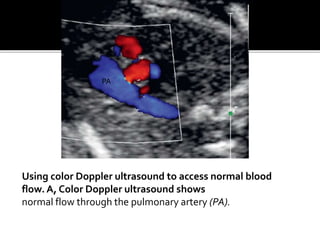

Using color Doppler ultrasound to access normal blood

flow. A, Color Doppler ultrasound shows

normal flow through the pulmonary artery (PA).

Using color Dopplerultrasound to access normal blood flow. A, Color Doppler ultrasound shows normal flow through the pulmonary artery (PA). PA